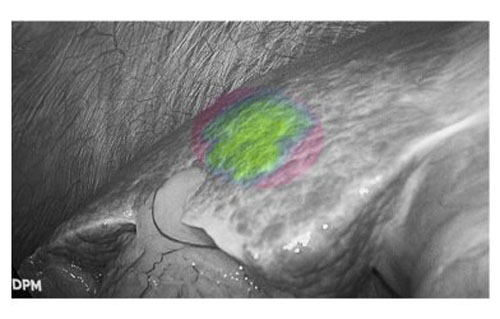

由于肝癌细胞对吲哚菁绿(ICG)代谢情况受损,因此通过荧光显影技术,病变细胞能够清晰呈现。这一特性不仅实现了肿瘤的精准定位,更使肿瘤边界清晰可见,帮助医生快速识别安全手术切缘,精准规划切除范围,在确保肿瘤完整切除的同时,最大限度保留健康肝组织。同时,避免误伤周围重要血管,显著提高了手术安全性,改善了患者的短期疗效和长期预后。

肝癌患者多合并肝硬化背景,而腹腔镜手术因缺乏触觉反馈,致使术者在微创条件下难以识别隐匿性病灶。吲哚菁绿(ICG)荧光显影技术通过术前静脉注射造影剂,可精准定位3毫米的原发性肝癌和肝转移癌。该技术有效弥补了腹腔镜肝胆手术中触觉反馈缺失的固有缺陷,为微创精准外科提供了重要技术支撑。

荧光显影技术,可精确显示肝内隐匿病灶

患者肝右后叶肝癌,根据三维重建精准阻断右后肝蒂,获得缺血线后进行荧光反染,显示肝脏切面的荧光和非荧光界面,助力解剖性肝右后区切除。

三维重建技术直观呈现肝段划分及血管、胆管解剖关系,而荧光显影技术则通过肝段染色,全程显露段间静脉,有助于识别肝内肝段间的界限,使肝胆外科医师可以全程实时观察肝脏切面变化,及时作出调整,优化手术方案,实现真正意义上的解剖性精准治疗。此外,吲哚菁绿(ICG)经胆道排泄的特性使术中胆管结构呈现清晰绿色荧光,大幅提升胆总管辨识度,有效降低腹腔镜手术中胆管损伤风险,为复杂肝胆手术安全性再添保障,显著降低了胆管损伤及相关并发症的发生率,进一步提升了手术安全性。